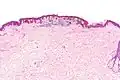

-

Low magnification

Low magnification -

Intermediate magnification

Intermediate magnification -

Very high magnification

Very high magnification